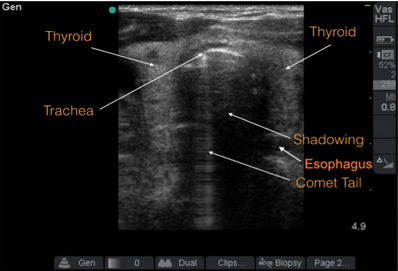

- Gently place the high-frequency linear probe just superior to the suprasternal notch in the transverse plane.

- The trachea will appear as a hyperechoic curvilinear structure with shadowing. A comet tail, or reverberation rings, appear deep to that structure.

- The esophagus will appear distally and to the right. It has a hyperechoic wall and hypoechoic center.

- Tracheal intubation: Visualize the second hyperechoic curvilenar structure within the trachea. You can also gently shake the ETT and visualize tracheal movement on the screen. Using Doppler, a color ray will also appear within the trachea.

- Esophageal intubation: The “double tract sign” (in which there seemingly appears to be two tracheas) indicates esophageal intubation.

- Pitfall: If the esophagus is anatomically located just posterior to the trachea, then the trachea’s shadowing may obscure an esophageal intubation.